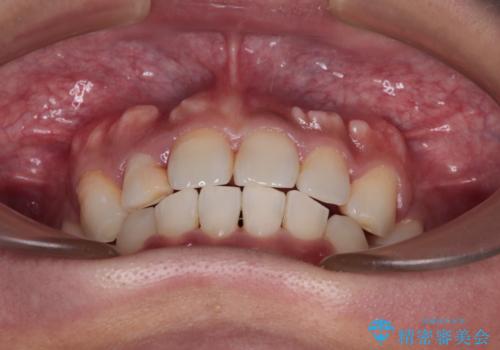

- 上顎の八重歯と正中のズレを気にして来院された患者様です。

八重歯による叢生は著しく、それにより上顎の正中が大きく右にずれている状態でした。

口元の突出感は感じていなかったことと、奥歯の咬み合わせを考慮し、上顎のみ左右の第一小臼歯を抜歯してワイヤー装置にて矯正治療を行うこととしました。

補助装置を併用することで効率的に八重歯や正中位置の改善を達成することができました。